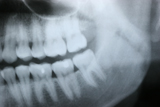

Wisdom Tooth Removal

Sometimes wisdom teeth are not functional, but instead create swelling and pain in the surrounding soft tissue, and they need to be taken out.

During the development of wisdom teeth, they often push away their neighboring teeth and contribute to anterior teeth crowding. Therefore, extraction of wisdom teeth is recommended in their early stage of eruption to prevent anterior crowding. The stress of eruption of wisdom teeth that grow horizontally causes dental decay on the 2nd molars and extraction is recommended before dental decay initiates.

Before / After